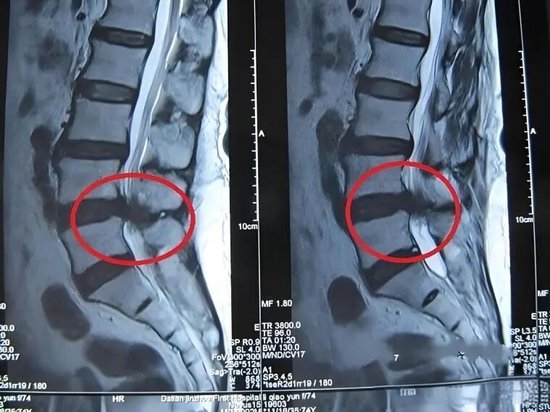

元凶二:高发隐患——腰椎间盘突出症

椎骨之间的椎间盘如同“软垫”,随年龄增长会退化、脱水,变得脆弱。在突然弯腰搬重物等不当用力后,椎间盘可能突出,压迫神经根,引发腰疼,还可能伴随臀部、大腿后侧、小腿甚至足底的放射性疼痛,以及腿脚麻木、无力、走路一瘸一拐等症状。

针对腰椎间盘突出症:椎间孔镜、UBE等微创手术

在内窥镜下精准摘除突出的髓核,解除对神经的压迫。手术切口仅1-2厘米,创伤小、出血少,多数患者术后次日即可在护具保护下下地活动,快速摆脱腰腿痛困扰。

他呼吁,老年朋友若出现持续腰疼或相关伴随症状,应尽早到医院通过X光片、核磁共振MRI等检查明确病因,及时接受针对性治疗。“腰疼是身体发出的重要警报,及时干预才能避免小毛病拖成大问题,让老年人拥有无痛、自由活动的晚年生活。”